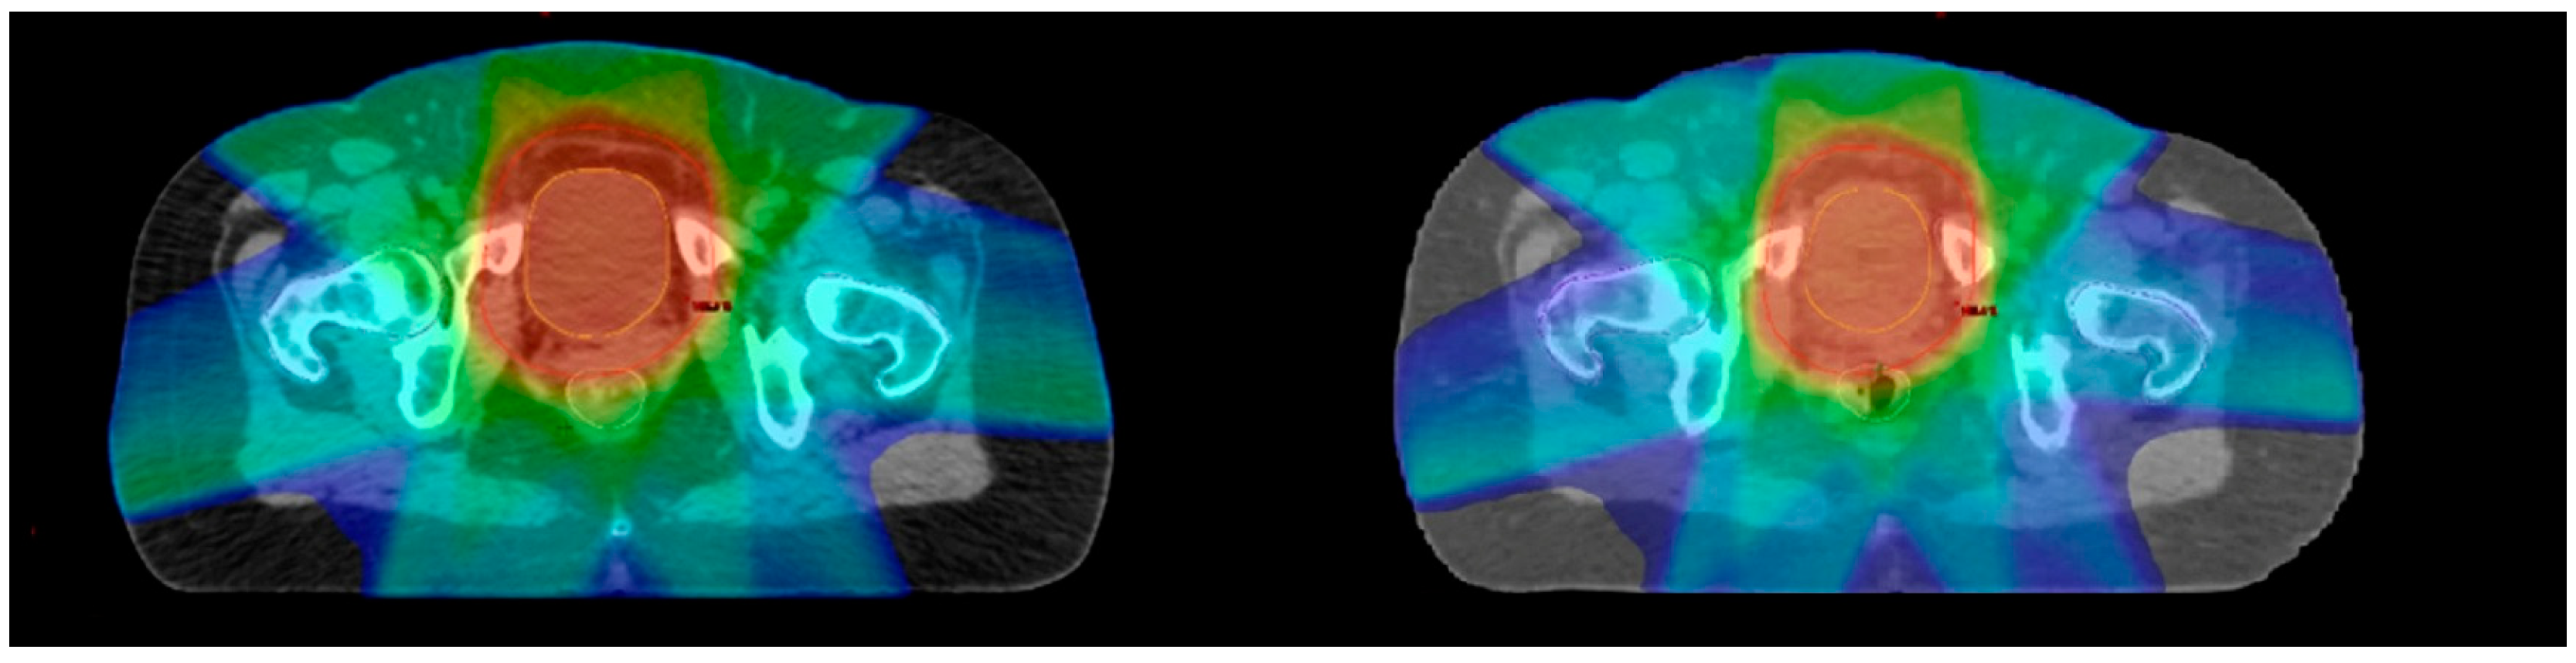

- Percentage volume covered by 95% of the prescription dose (V95% [%]).

- Percentage volume covered by 105% of the prescription dose (V105% [%]).

- Near-maximum dose in Gy, which is the dose covering 2% of the PTV volume (D2%[Gy]).

- Near-minimum dose in Gy, which is the dose covering 98% of the PTV volume (D98%[Gy]).

- Median dose in Gy, which is the dose covering 50% of the PTV (D50%[Gy]).